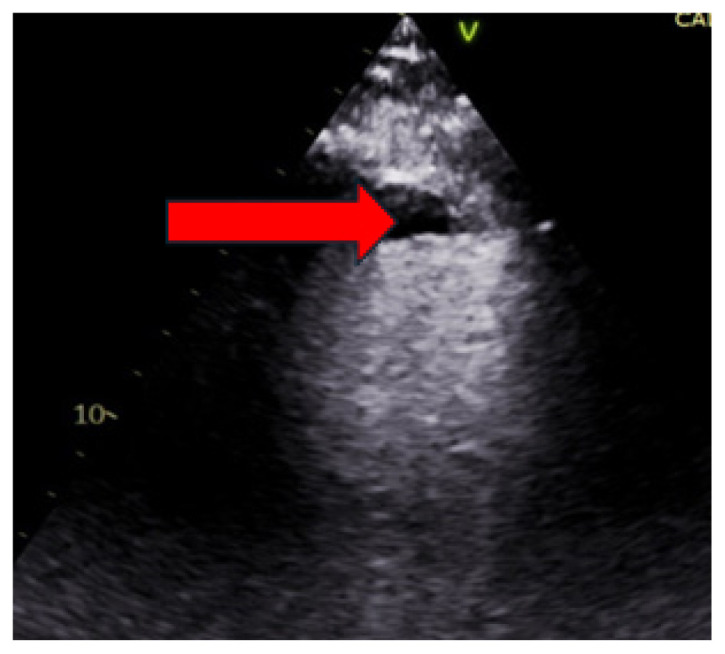

反向分析:左室血栓引起的脾梗死。

Working Backwards: Splenic Infarcts from Left Ventricular Thrombus.